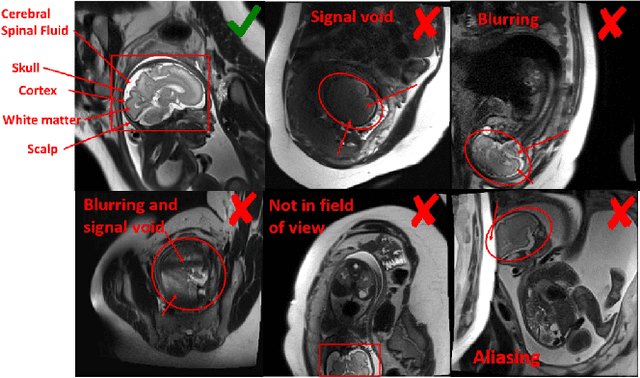

Abstract:Fetal brain MRI is useful for diagnosing brain abnormalities but is challenged by fetal motion. The current protocol for T2-weighted fetal brain MRI is not robust to motion so image volumes are degraded by inter- and intra- slice motion artifacts. Besides, manual annotation for fetal MR image quality assessment are usually time-consuming. Therefore, in this work, a semi-supervised deep learning method that detects slices with artifacts during the brain volume scan is proposed. Our method is based on the mean teacher model, where we not only enforce consistency between student and teacher models on the whole image, but also adopt an ROI consistency loss to guide the network to focus on the brain region. The proposed method is evaluated on a fetal brain MR dataset with 11,223 labeled images and more than 200,000 unlabeled images. Results show that compared with supervised learning, the proposed method can improve model accuracy by about 6\% and outperform other state-of-the-art semi-supervised learning methods. The proposed method is also implemented and evaluated on an MR scanner, which demonstrates the feasibility of online image quality assessment and image reacquisition during fetal MR scans.